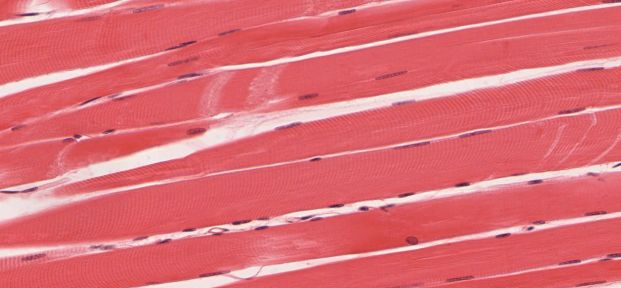

Immagine: tessuto muscolare scheletrico. Credit: University of Michigan Medical School

Le cellule staminali specializzate, conosciute come cellule satelliti, risiedono nei muscoli scheletrici, in uno stato di inattività o quiescenza. Quando si verifica un infortunio muscolare, una catena di segnali induce le cellule satelliti a risvegliarsi e generare nuove cellule muscolari per riparare il danno. Come parte di questo processo, le cellule satellite si auto-rinnovano al fine di ricostituire il pool di cellule satelliti per eventuale altra riparazione del muscolo in futuro.